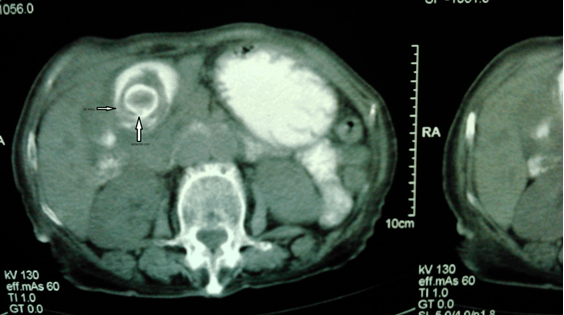

An abdominal CT scan was performed showing inflammatory gallbladder wall with a cyst within cyst appearance (Figure 1). Hepatic parenchyma and other abdominal organs proved absolutely normal.

Figure 3: Computed tomography scan showing inflammatory gallbladder wall with a cyst within cyst appearance.